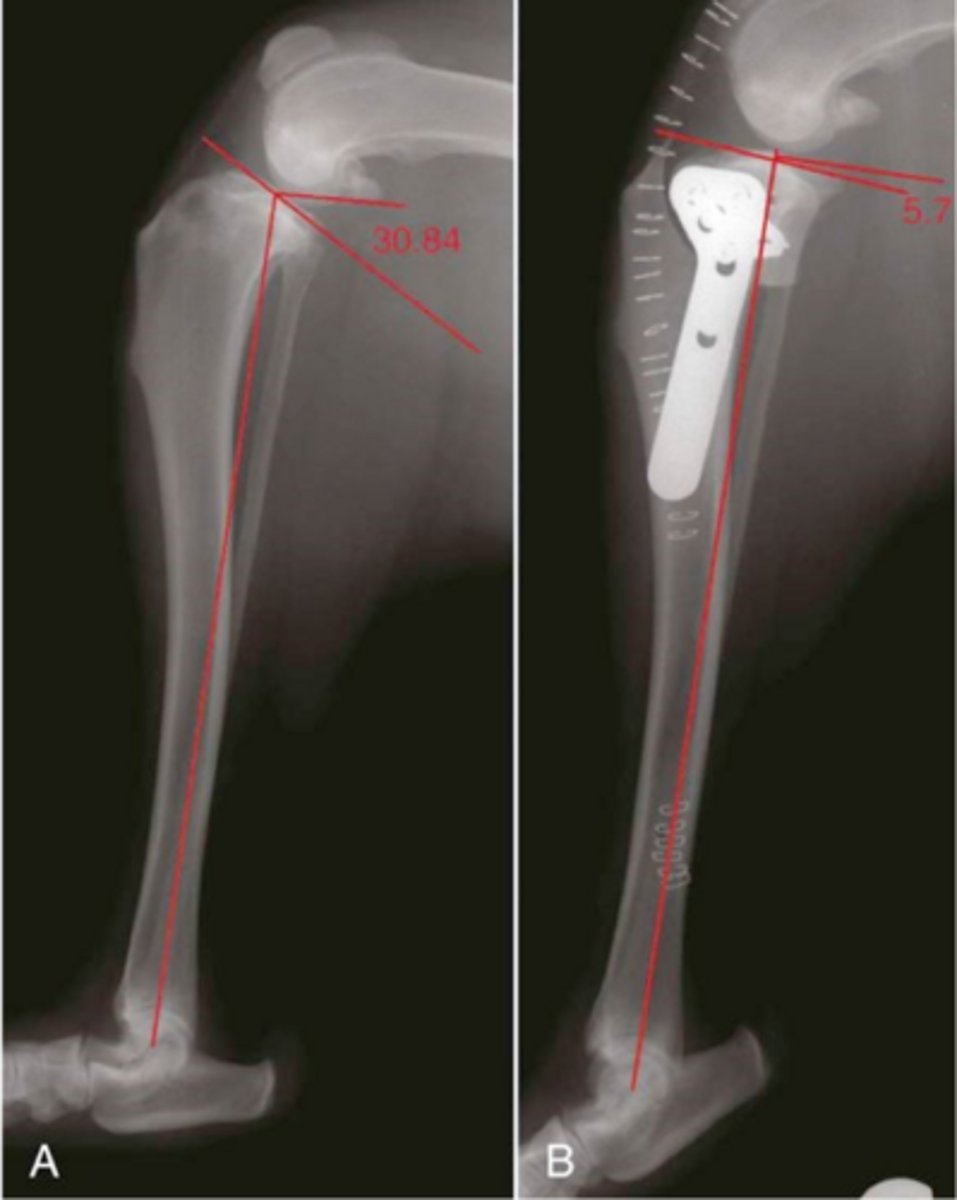

RADs of. TPLO dog to a slope of 5 degrees

what is shown here

RADS for a (TWO) tibial wedge osteotomy dog